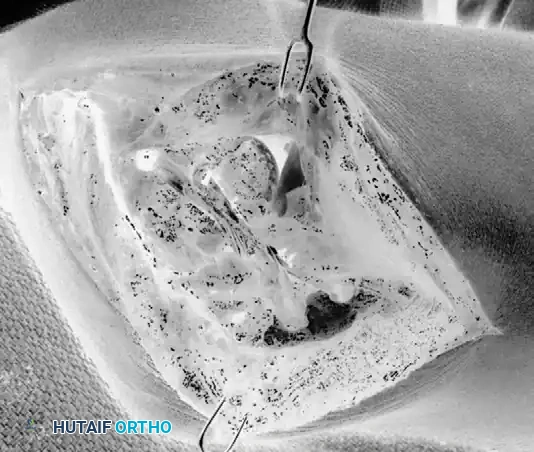

1. The Modified Kocher Approach

Approach the elbow through a modified Kocher incision. The incision begins approximately 5 cm proximal to the lateral epicondyle, extending distally across the epicondyle, and curving slightly anteriorly toward the radial head, ending at the level of the annular ligament.

- Superficial Dissection: Incise the deep fascia in line with the skin incision. Identify the internervous plane between the anconeus (innervated by the radial nerve) and the extensor carpi ulnaris (ECU, innervated by the posterior interosseous nerve).

- Deep Dissection: By sharp dissection, carefully elevate the common extensor origin, including a portion of the extensor carpi radialis brevis (ECRB), to reveal the origin of the radial collateral ligament complex at the lateral epicondyle.

2. Exposure of the Ligamentous Complex

Distally, reflect the anconeus muscle posteriorly and the extensor carpi ulnaris anteriorly. Reflect the extension of the origin of the anconeus to the lateral aspect of the triceps fascia sufficiently to expose the ligament adequately.

Identify the supinator crest (crista supinatoris) of the ulna. This bony ridge is the anatomic insertion site of the LUCL and serves as the primary landmark for ulnar tunnel placement. Typically, upon exposure, a lax ulnar band of the radial collateral ligament is observed, and the abnormal, attenuated portion of the ligament is identified.